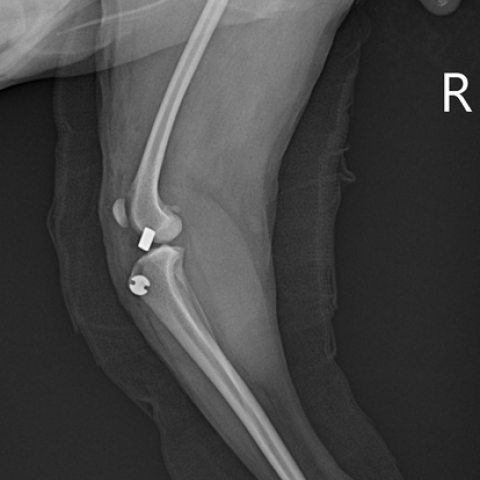

Àü½ÊÀÚ Àδ밡 ²÷¾îÁø µÚ ¾à 2´Þ Áö³ª¸é ´ëºÎºÐÀÇ ¼ÒÇü°ßµéÀº ¼ö¼ú ¾øÀ̵µ ²Ï Àß °É¾î¿ä. ÇÏÁö¸¸ ÃßÈÄ¿¡ ½ÉÇÑ °ñ°üÀý¿°ÀÌ »ý±â°í ÀÌ·Î ÀÎÇØ ÀÚÁÖ ´Ù¸®¸¦ Àý·èÀÌ¸ç °íÅëÀ» È£¼ÒÇÒ°Å¿¹¿ä. ±×·¯´Ï ¸¶Ãë°¡ ±Øµµ·Î À§ÇèÇÑ »óȲÀÌ ¾Æ´Ï¶ó¸é ¼ö¼úÀ» ÇÏ´Â °Ô ÁÁ¾Æ¿ä.

TPLO, CTWO, ECF µî ´Ù¾çÇÑ ¼ö¼ú ¹æ¹ýÀÌ ÀÖ¾î¿ä. ±× Áß TPLO°¡ °¡Àå ¿¹Èİ¡ ÁÁ¾Æ¿ä. ´Ù¸¥ ¼ö¼ú¹æ½Ä¿¡ ºñÇØ »¡¸® ȸº¹µÇ°í ºÎÀÛ¿ëµµ ´ú ÇÑ ÆíÀÌÁÒ. ÇÏÁö¸¸ ¸ðµç ¼ö¼úÀº ¼·Î ´Ù¸¥ Àå´ÜÁ¡À» °¡Áö°í ÀÖ°í °æ¿ì¿¡ µû¶ó TPLO°¡ ºÒ°¡´ÉÇÑ ¾ÆÀ̵éÀÌ ÀÖ¾î¿ä. ÀÌ·² °æ¿ì ´Ù¸¥ ¹æ½ÄÀÇ ¼ö¼úÀ» ÁøÇàÇØ¾ß µÅ¿ä.

½ÊÀÚÀδ밡 ²÷¾îÁø ¾ÆÀÌ´Â 2³â À̳»·Î ¹Ý´ëÂÊ ½ÊÀÚÀδ밡 ²÷¾îÁú È®·üÀÌ 50% °¡±îÀÌ µÇ¾î¿ä. ±×·¯´Ï À̸¦ ¿¹¹æÇϱâ À§ÇÑ °ü¸®°¡ ÇʼöÀûÀÌÁÒ. ÇÑ ¹øÀÇ ¼ö¼ú ÈÄ ¹æÄ¡ÇÏÁö ¾Ê°í °üÀý¿°°ú ¹Ý´ëÂÊ ´Ù¸®ÀÇ ½ÊÀÚÀÎ´ë ´Ü¿À» ¿¹¹æÇϱâ À§ÇØ Áö¼ÓÀûÀÎ °ü¸®¸¦ ÇØ¿ä.